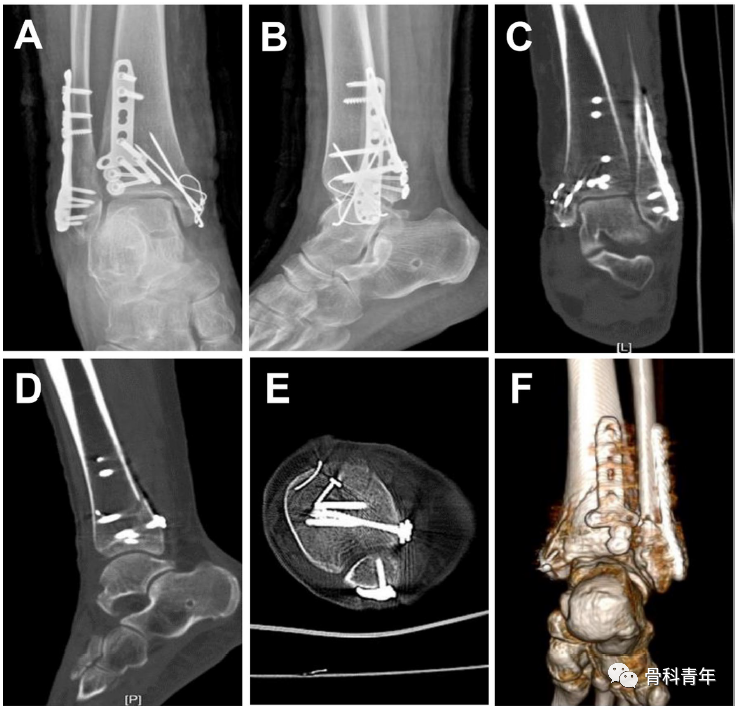

病例2: